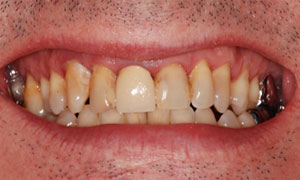

A l’issue de son traitement parodontal, le patient âgé de 60 ans souhaite modifier son sourire.

Il souhaite avoir des espaces interdentaires moins volumineux et avoir des dents du haut et du bas bien alignées.

Une maquette en cire sur des modèles ( WAX UP) permet de montrer le projet au patient et d’apporter des corrections si nécessaires.

Le projet en résine (MOCK UP) est appliqué sur les dents pour être validé une seconde f ois par le patient et pour servir de guide de préparation dentaire pour le praticien.

Les 8 facettes sont collées le surlendemain.

Les espaces interdentaires ont été fermés conformément au projet, tout en laissant un passage pour des brossettes interdentaires de taille inférieure. Les lignes interincisives coïncident dans le sens vertical conformément au projet et aux souhaits du patient.